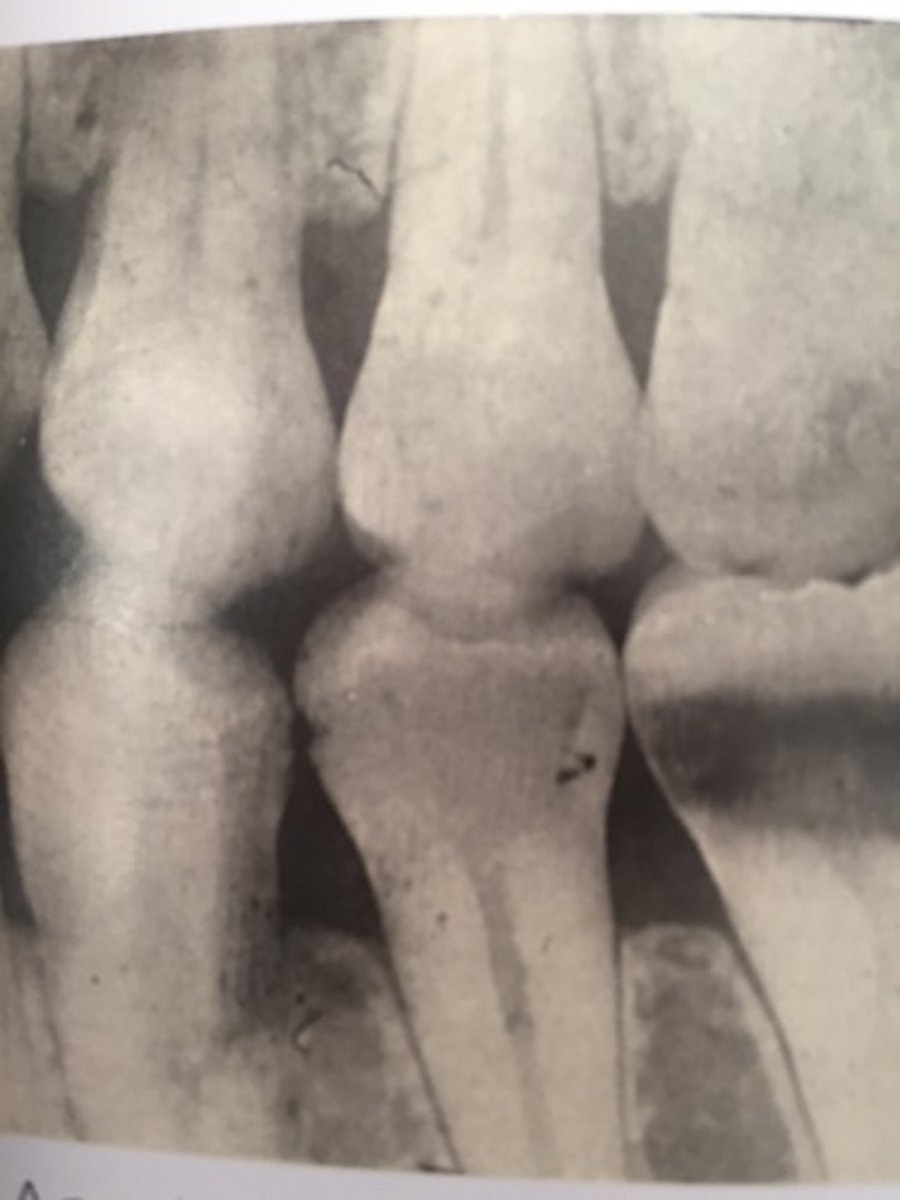

mandibular canal

border on top and bottom by a white line

passageway for nerves and blood vessels